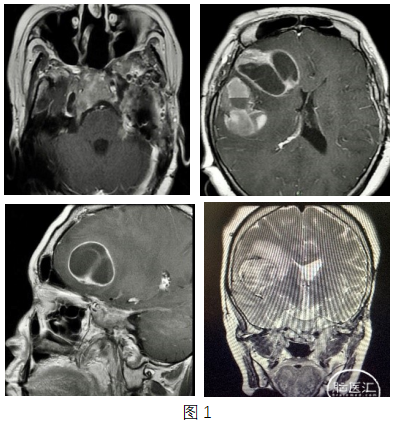

年轻女性,因“垂体瘤多次术后放疗后,发现复发4月余”入院。该患者自2012年起因垂体瘤先后七次行经鼻蝶手术及开颅手术和一次V-P分流,术后病理均提示垂体腺瘤。入院查体精神差,认知功能下降。2020年7月查头颅MRI提示鞍区肿瘤复发进展,且右侧额、顶叶分别见5*4cm及5*3cm大小的占位,鞍区占位T2WI/FLAIR呈中高信号,增强可见明显的不均匀强化。右侧额叶占位,T2WI/FLAIR呈等信号,边缘大片水肿,增强可见边缘实性成分及内部分隔明显强化。右侧顶叶囊实性病变,T2WI/FLAIR呈混杂等高信号伴囊内液平,增强可见边缘实性成分明显强化,病变周围见大片水肿(图1)。血清皮质醇:1.86nmol/L(参考值166-507nmol/L),泌乳素1495 uIU/ml(参考值102-496 uIU/ml),TSH 0.214 uIU/ml(参考值0.27-4.2 uIU/ml),生长激素正常范围。